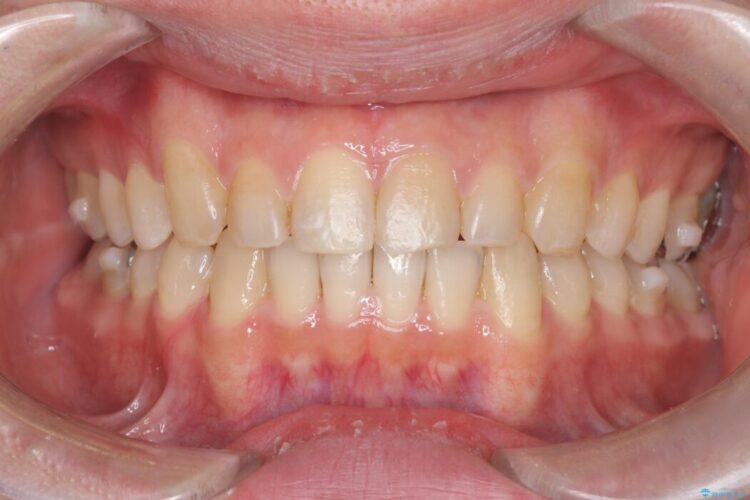

歯の隙間とデコボコ、シザーズバイトも改善され、咬み合わせや見た目が整い、患者様にも大変ご満足いただけました。